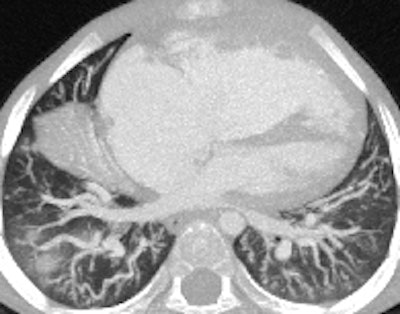

A 14-year-old patient with transposition of greater arteries and gross pulmonary arterial hypertension. CT angiography study shows aneurysmal dilation of the pulmonary arteries (top left, top right), with thrombus in the right middle lobe pulmonary artery (bottom left). There is partial anomalous pulmonary venous return from the right upper lobe to the superior vena cava (arrow, bottom right).